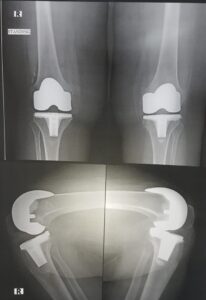

The goal of total knee replacement surgery is to relieve pain and restore the alignment and function of your knee.

The surgery is performed under spinal or general anesthesia. Your surgeon will make an incision in the skin over the affected knee to expose the knee joint. Then the damaged portions of the femur bone are cut at appropriate angles using specialized jigs. The femoral component is attached to the end of the femur with or without bone cement. The surgeon then cuts or shaves the damaged area of the tibia (shinbone) and the cartilage. This removes the deformed part of the bone and any bony growths, as well as creates a smooth surface on which the implants can be attached. Next, the tibial component is secured to the end of the bone with bone cement or screws. Your surgeon will place a plastic piece called an articular surface between the implants to provide a smooth gliding surface for movement. This plastic insert will support the body’s weight and allow the femur to move over the tibia, similar to the original meniscus cartilage. The femur and the tibia with the new components are then put together to form the new knee joint. To make sure the patella (knee cap) glides smoothly over the new artificial knee, its rear surface is also prepared to receive a plastic component. With all the new components in place, the knee joint is tested through its range of motion. The entire joint is then irrigated and cleaned with a sterile solution. The incision is carefully closed, drains are inserted and a sterile dressing is placed over the incision.